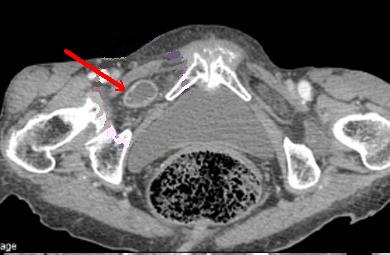

| Hernie inguinale etranglee : Image TDM en

coupe axiale a travers L5 |

|

Hernie

inguinale etranglee : Meme cas en coupe axiale a

travers symphyse pulbienne |

| Hernie inguinale etrangle : Image

d'engage du grele dans fossette inguinale

moyenne + image de distension de l'intestin au

dessus de l'obstacle ( fleche rouge ) . |

La TDM est tres

l'interet de presiser facilement le type de hernie :

hernie inguinale direct etrangle avec image de grele

en de dans des vaisseaux epigastriques .La TDM peut

differentiele avec les autres masses de la region

scrotale . |